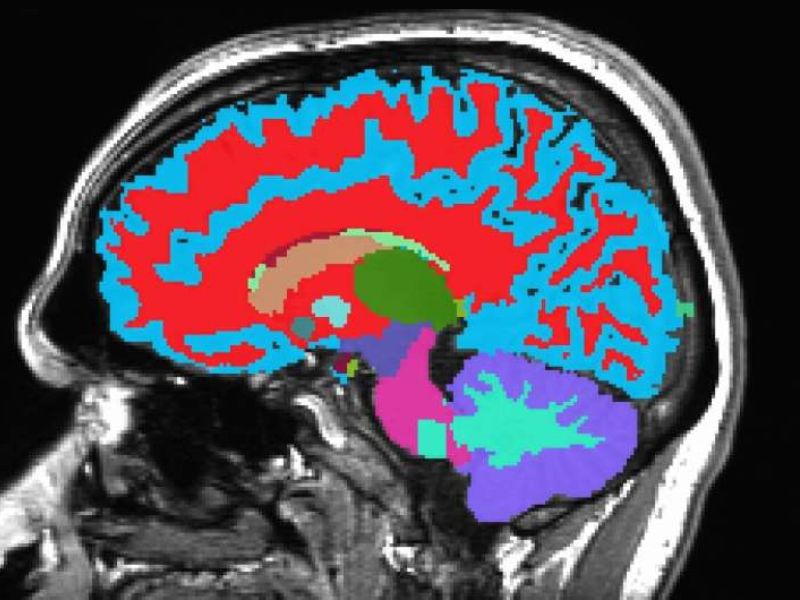

They then developed a tool called DunedinPACE Neuroimaging (DunedinPACNI) that uses just one brain MRI to estimate this rate. Trained on scans from 860 participants at age 45, the tool was later validated using brain imaging data from the U.K., U.S., Canada, and Latin America.